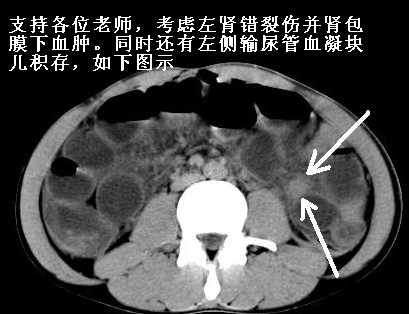

支持各位老师!

左肾挫裂伤伴肾周血肿

左侧少量腹水

左肾没有积水,输尿管位置应该靠内侧.所以守望可可西里老师所指左侧输尿管血凝块,连续看应该是肠管.

我不同意守望可西里老师所说的有输尿管的血液凝积一说,首先从这个图像来看输尿管的走行太偏外了,输尿管是肾盂向下延续的部分,开始在腰大肌的外缘,逐渐向内偏移,接近或越过腰椎横突的外端。而守望可可西里老师所指的这段图像位置太靠外了,且总是伴行在一段肠管的前缘。第二,如果有血液的凝积,可造成肾盂肾盏的扩张积水,而这个病人的肾盂肾盏的形态一直很好。